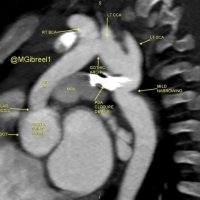

[gallery ids="16664"] Mohamed Gibreel , FEBR (Fellowship of Egyptian Board of Radiology ) Cardiac imaging consultant at Aswan heart center -Magdi Yacoub Foundation , Egypt